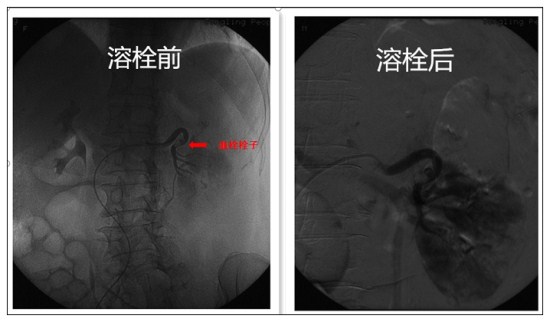

2018年12月31日,刘女士一家欢天喜地的出院了。该患者既往有房颤病史,12月23日突发左腰部剧烈疼痛,来我院就诊,次日明确诊断为肾动脉栓塞后转入血管病区。此时患者腰部疼痛进一步加剧,如不及时开通肾动脉,患者即将面临左肾缺血坏死,甚至进一步发生感染可能。经病例讨论后,血管病区立即为该患者行肾动脉置管溶栓术。术后患者腰痛症状明显缓解,术后第二天造影提示左肾动脉血供大部分恢复,出院时肾功能正常。一根导丝、一根导管,住院一周,以极小的代价保住了患者一侧肾脏。2018年完美收官!